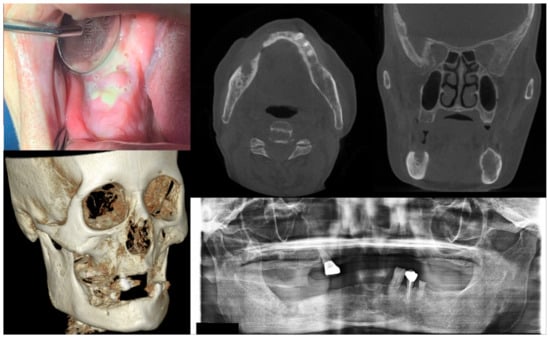

Figure 4.

Case 4 with MRONJ Stage 3: Clinical photo, panoramic view, and computed tomography imaging including three-dimensional reconstruction showing extraoral fistula and necrotic bone on the mandibular left anteroposterior area. An 80-year-old female patient with a history of intravenous administration of ibandronate and denosumab for one year was presented with inflammation and skin fistula on the chin area. She had undergone periodontal treatment on the left lower posterior teeth three months ago due to a periodontal abscess, but she was referred for recurrence with facial swelling from a private dental clinic. Bony lesions involving the inferior border of the mandible and the presence of extraoral fistula were observed.